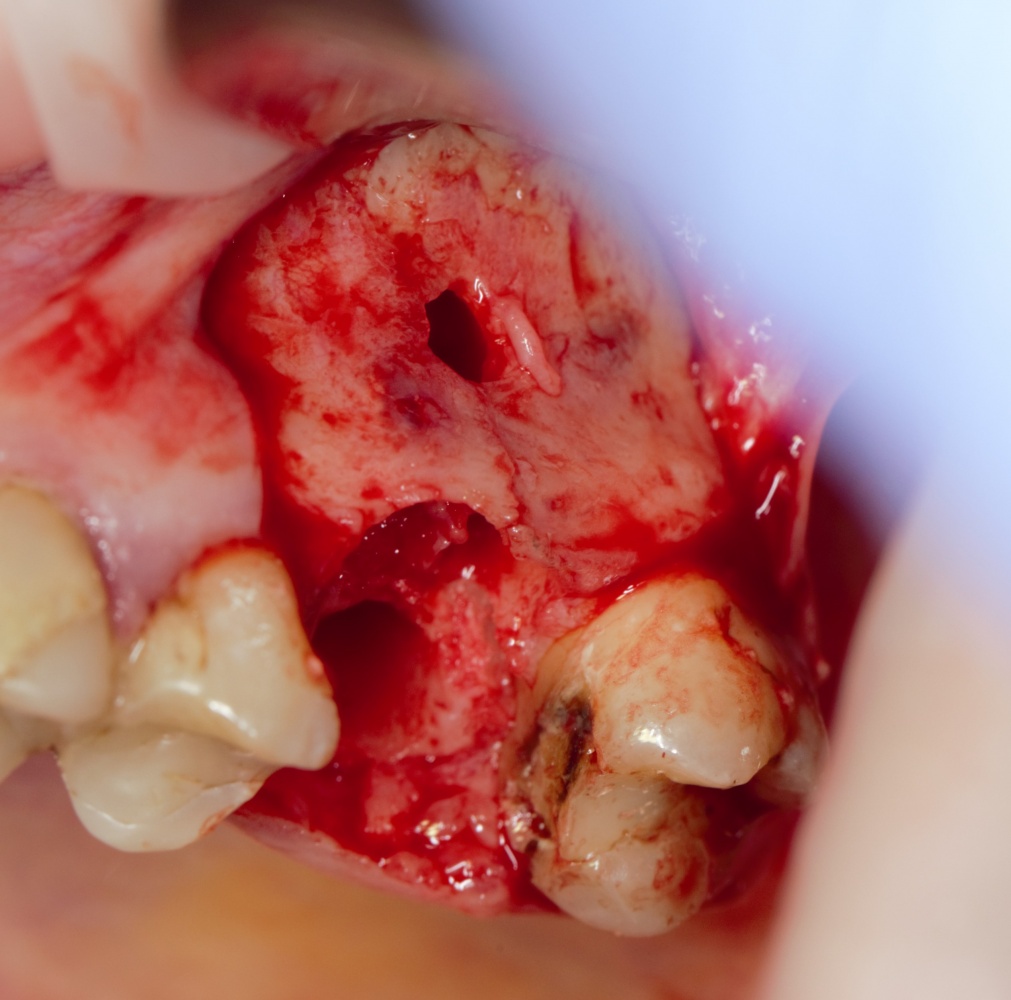

Как на фотографии выше — из-за целого ряда вмешательств и существовавшего ранее ороантрального соустья можно сказать, что от слизистой оболочки верхнечелюстной пазухи почти ничего не осталось. Можем ли мы как-то закончить эту работу? Легко: